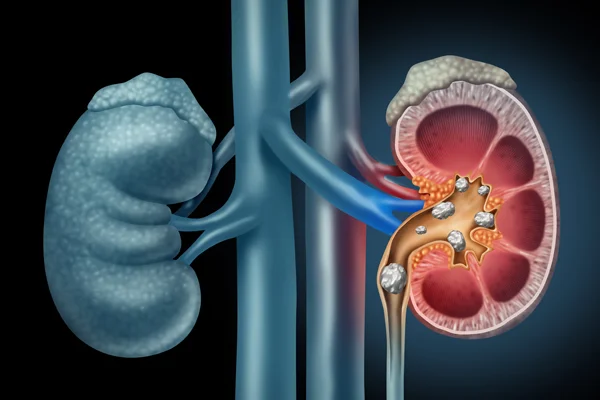

Kidney stones are hard deposits made of minerals and salts that form inside the kidneys. They can vary in size and may cause severe pain when they move into the urinary tract.

These stones can block the flow of urine, leading to discomfort, infection, or other complications if not treated in time.

Kidney stones are of different types depending on the minerals that form them.

• Calcium Stones: The most common type, formed when calcium combines with other substances in urine and creates hard crystals.

• Uric Acid Stones: Form when urine becomes too acidic, often seen in people who consume high amounts of meat or drink less water.

• Struvite Stones: Usually develop after urinary tract infections and can grow quickly if not treated.

• Cystine Stones: Rare stones caused by a genetic condition, and may recur in some patients.